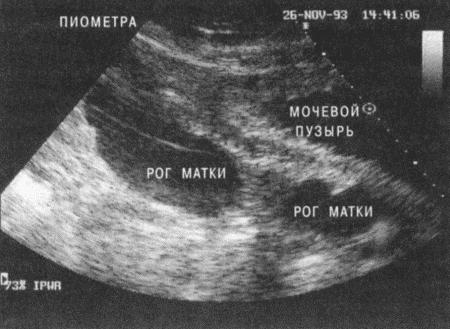

• пальпацию брюшной полости для выявления плодов или патологий матки (опухолей, увеличения матки из-за пиометры).